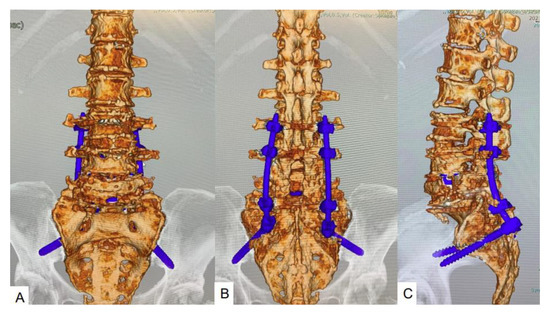

脊椎脊髄の手術 = Illustrated Surgery of Spine … 脊椎脊髄の手術 = Illustrated Surgery of Spine …の詳細情報

脊椎脊髄の手術 = Illustrated Surgery of Spine …。Medical Illustration | Lumbar Spine Injuries Followed By。Atlas of Image-Guided Spinal Procedures: Furman MD, Michael。Postoperative cage migration and subsidence following TLIF。「脊椎脊髄の手術 = Illustrated Surgery of Spine & Spinal Cord 第2巻」戸山 芳昭 / 花北 順哉定価: ¥ 24000#戸山芳昭 #戸山_芳昭 #花北順哉 #花北_順哉 #本 #自然/医療・薬学・健康